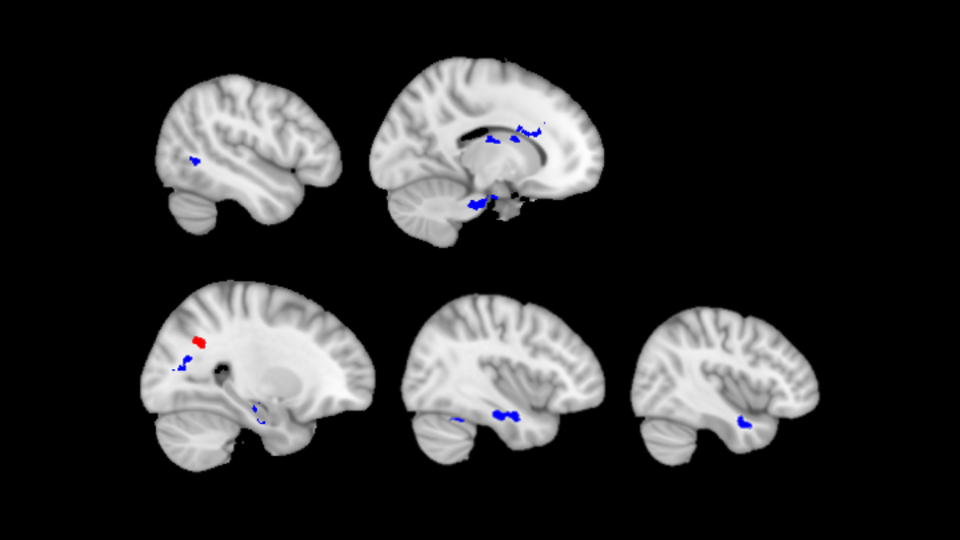

After undergoing the MRI scan, the students completed a demographic assessment and the Childhood Trauma Questionnaire, which asked about the history of physical abuse. The MRI scans showed structural differences in the brains of students who suffered physical child abuse. Several white matter tracts, bundles of long slender projections of nerve cells that connect distinct regions of the brain, showed decreased cohesiveness in those students.

The study showed reduced cohesion of white matter tracts connecting areas of the brain related to behavioral and emotional controls, memory processing, and a relay of sensory and motor signals. Some of the alterations are similar to those found in previous studies showing how verbal abuse and traumatic events affect white matter structure, but others were unique to the effects of physical abuse.